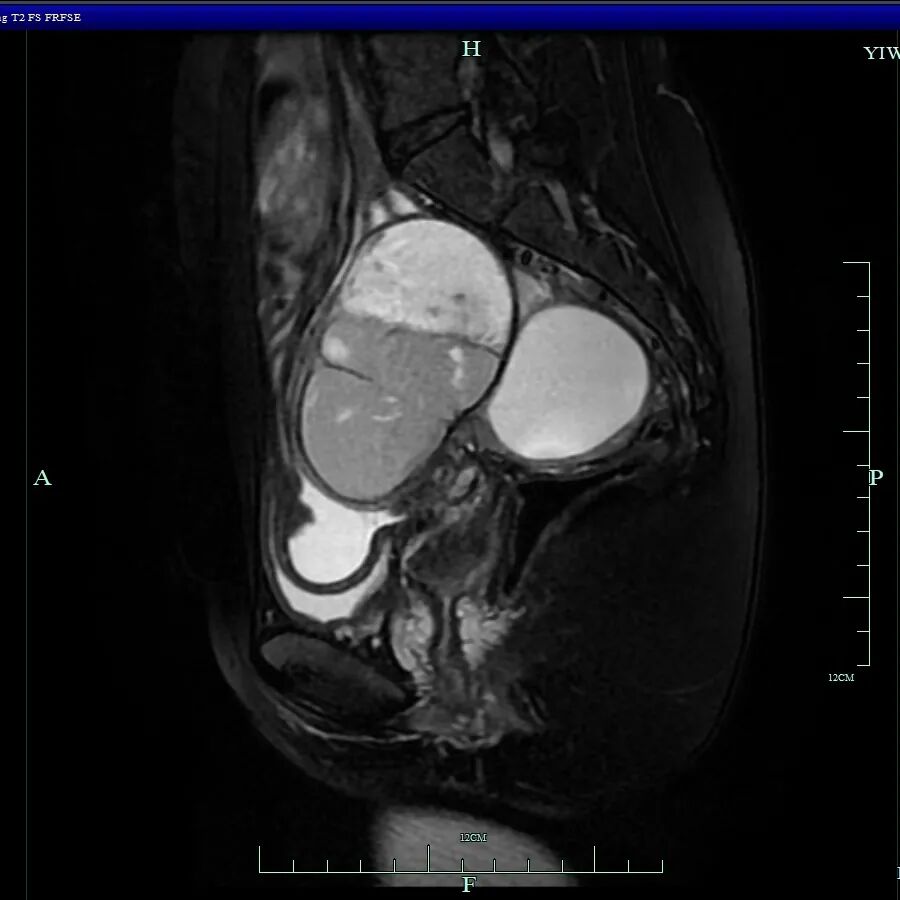

妇科主任吴萍为其详细检查后,诊断为卵巢子宫内膜异位囊肿、子宫内膜异位症四期(重度)、子宫腺肌病、肠道子宫内膜异位症

术中发现其盆腔内器官广泛严重粘连,右侧卵巢有直径约10厘米的囊肿,左侧卵巢亦有囊肿,并在直肠前壁等多处发现异位病灶。手术团队凭借精湛技术成功分离粘连,精准切除了所有病灶,并修复受损组织,保住了生育器官,手术圆满完成。

· 形成囊肿:如在卵巢上,陈旧性血液积聚形成咖啡色、粘稠的囊肿,俗称“巧克力囊肿”。

· 造成粘连:血液的刺激会导致盆腔内器官相互粘连,像胶水一样粘在一起,引发长期慢性盆腔痛和不孕。

· 侵犯器官:异位内膜可深入侵犯肠道、膀胱、输尿管,引起便血、便秘、尿血、肾积水等严重并发症,正如小杨所遭遇的一样。